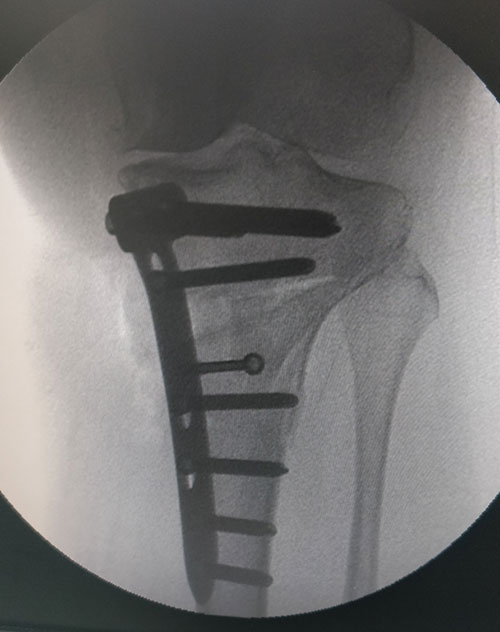

STEPS OF HTO